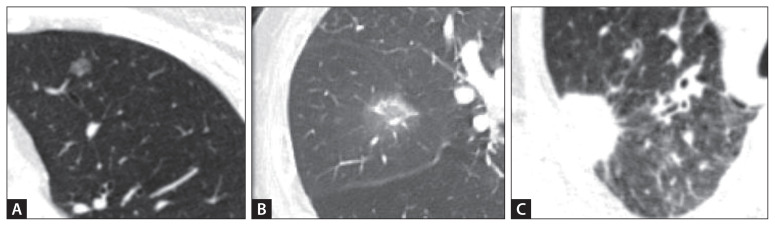

肺癌仍然是世界范围内癌症相关死亡的主要原因,通常在晚期被诊断出来,生存率很差。偶发性肺结节的早期发现和适当处理,通常通过低剂量计算机断层扫描发现,对于改善预后和降低肺癌死亡率至关重要。已建立的指南,包括Fleischner协会和美国放射学会的指南,为风险评估、监测和干预提供了结构化的建议。诊断方法的最新进展,如正电子发射断层扫描、支气管内超声、电磁导航支气管镜检查和机器人辅助支气管镜检查,提高了诊断的准确性,同时最大限度地降低了手术风险。结合这些技术的多学科方法对于优化患者护理至关重要。本文综述了目前评估和治疗孤立性肺结节的策略,包括风险分层模型、影像学特征和活检技术,从而为临床医生提供了一个全面的概述。

Lung cancer remains a leading cause of cancer-related mortality worldwide and is often diagnosed at an advanced stage, with poor survival outcomes. Early detection and appropriate management of incidental pulmonary nodules, frequently identified through low-dose computed tomography screening, are critical for improving prognosis and reducing lung cancer mortality. Established guidelines, including those of the Fleischner Society and American College of Radiology, provide structured recommendations for risk assessment, surveillance, and intervention. Recent advancements in diagnostic modalities, such as positron emission tomography, endobronchial ultrasound, electromagnetic navigation bronchoscopy, and robot-assisted bronchoscopy, have enhanced the diagnostic accuracy while minimizing procedural risks. A multidisciplinary approach that incorporates these technologies is essential for optimizing patient care. This review summarizes the current strategies for evaluating and managing solitary pulmonary nodules, including risk stratification models, imaging features, and biopsy techniques, thereby providing a comprehensive overview for clinicians.